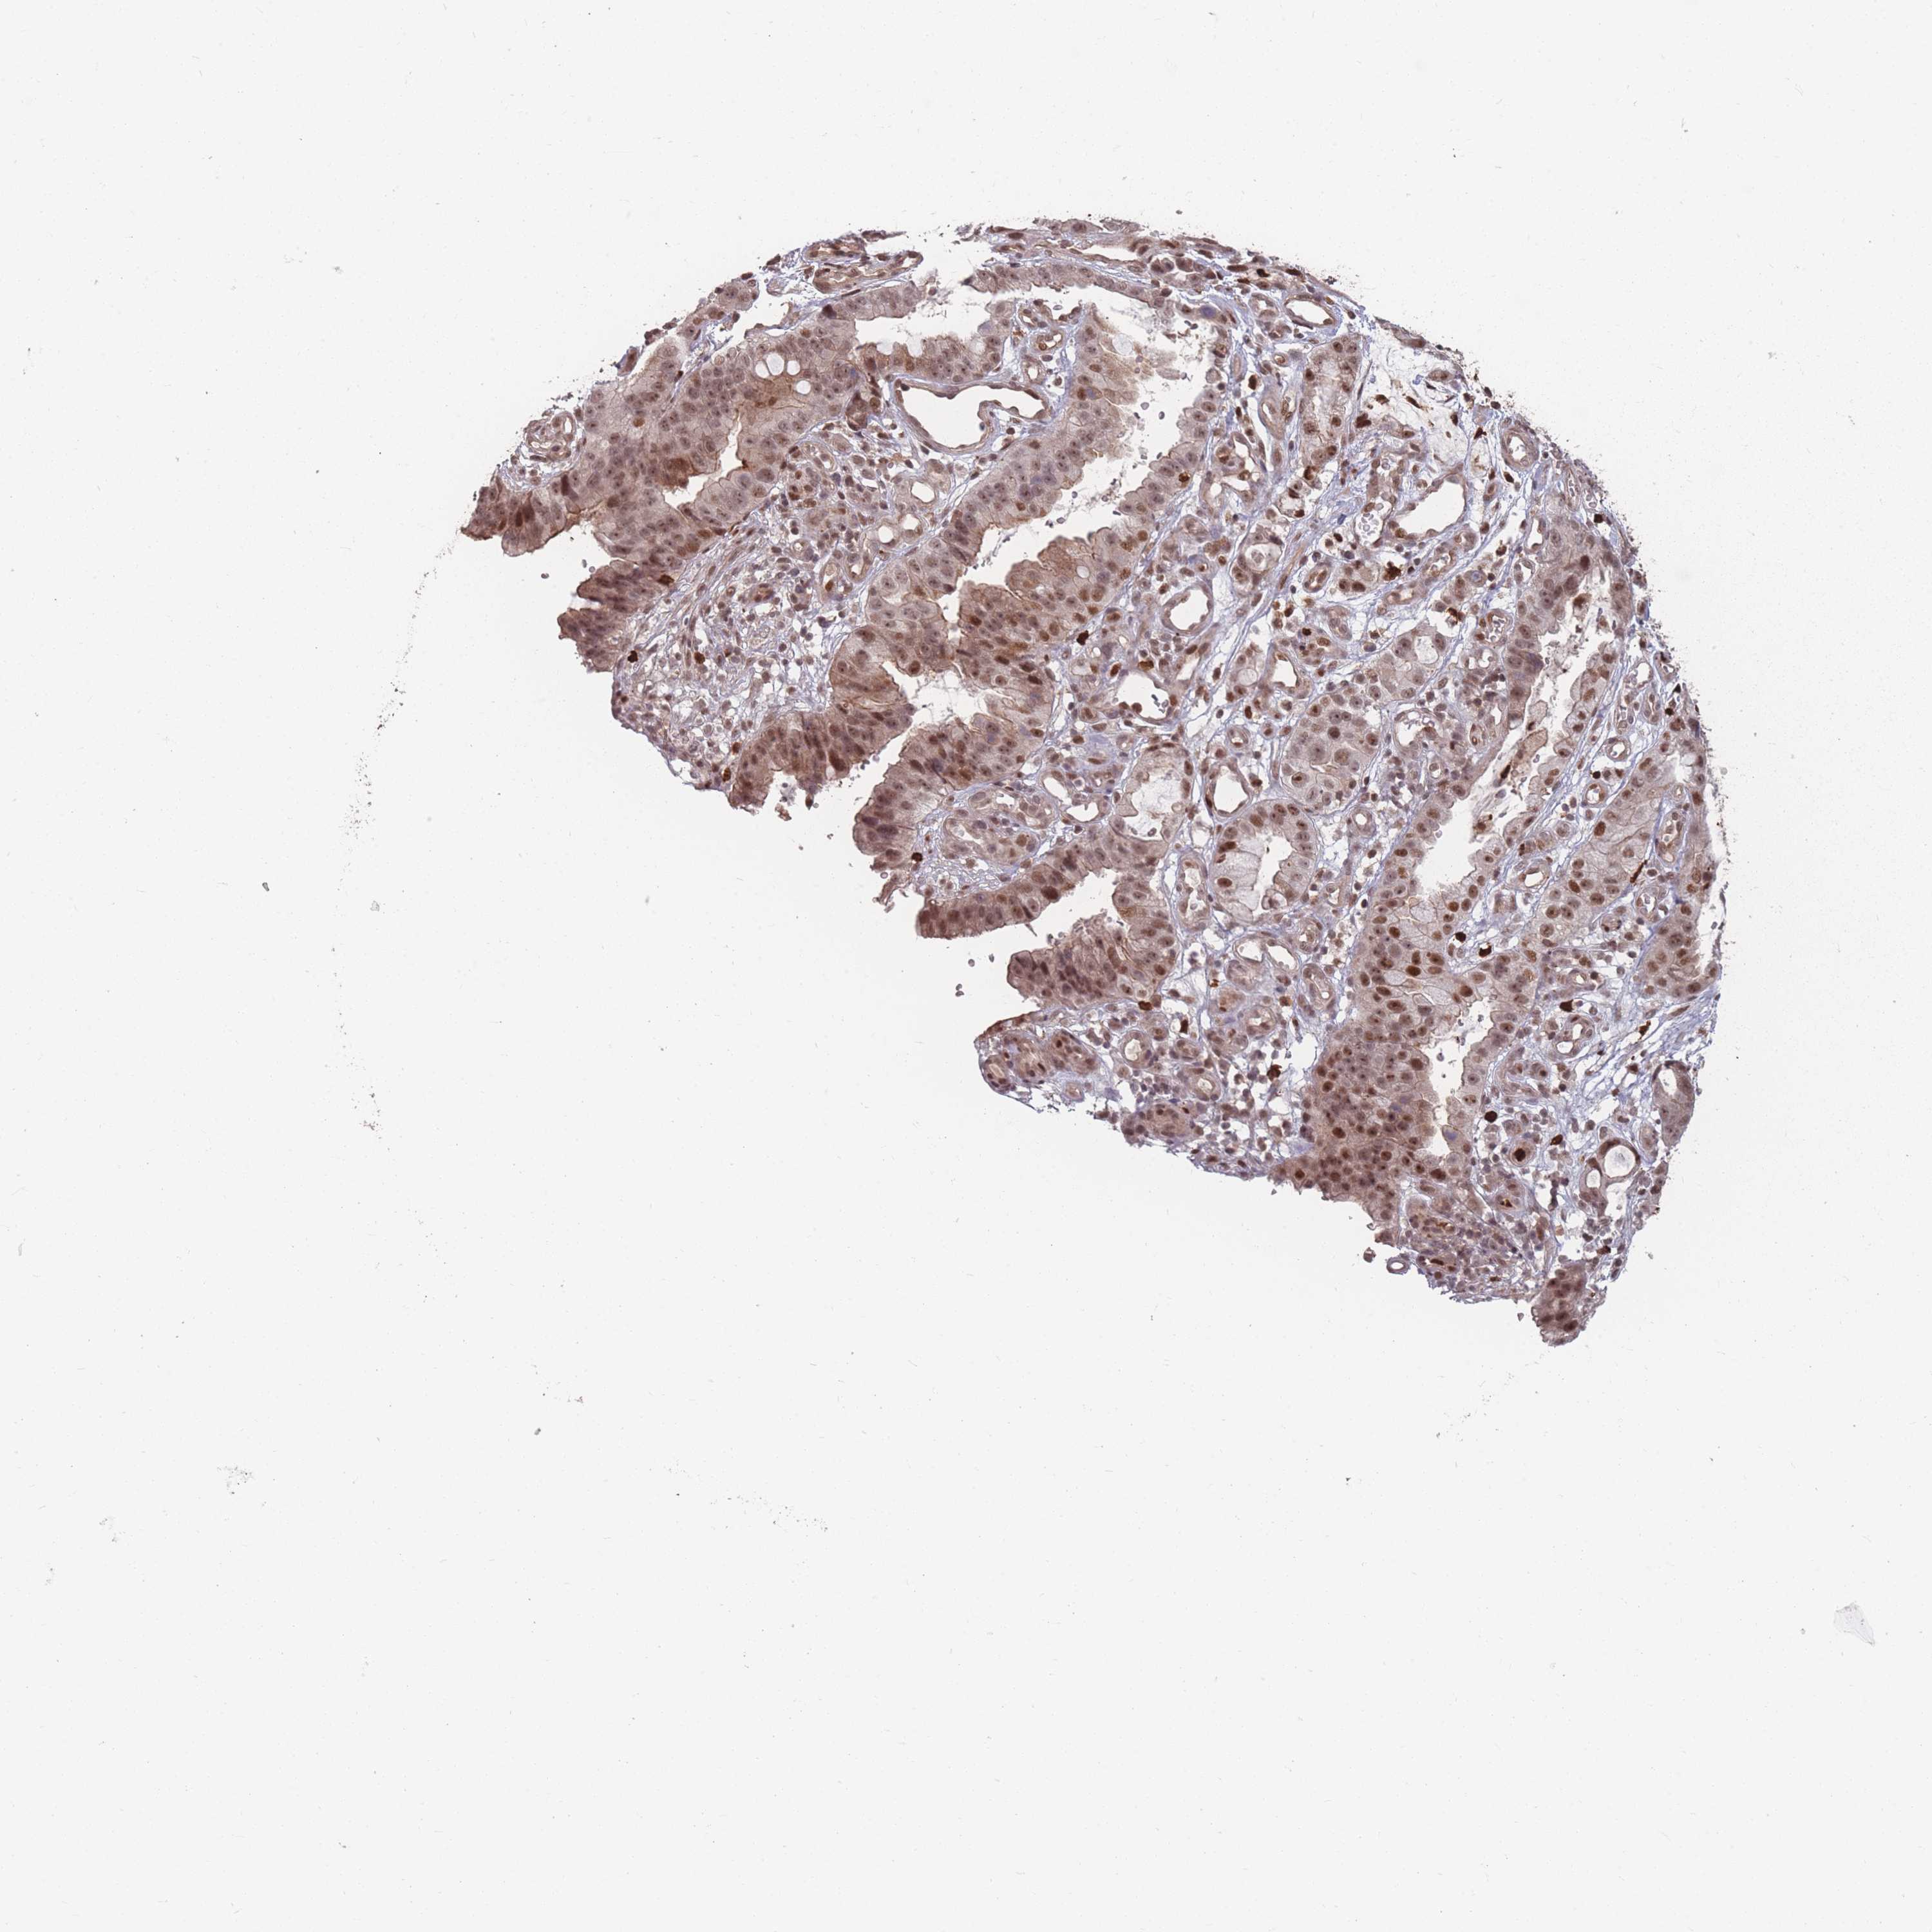

STOMACH CANCER - Protein expressioni

A mouse-over function shows sample information and annotation data. Click on an image to view it in a full screen mode. Samples can be filtered based on level of antibody staining by selecting one or several of the following categories: high, medium, low and not detected. The assay and annotation is described here.

Note that samples used for immunohistochemistry by the Human Protein Atlas do not correspond to samples in the TCGA dataset.

Antibody stainingi

Antibody staining in the annotated cell types in the current human tissue is reported as not detected, low, medium, or high, based on conventional immunohistochemistry profiling in selected tissues. This score is based on the combination of the staining intensity and fraction of stained cells.

Each image is clickable and will lead to virtual microscopy that enables deeper exploration of all samples and also displays staining intensity scores, fraction scores and subcellular localization as well as patient and tissue information for each sample.

Antibody HPA043470

Antibody HPA048143

Staining

High

Medium

Low

Not detected

Intensity

Strong

Moderate

Weak

Negative

Quantity

>75%

75%-25%

<25%

None

Location

Nuclear

Cytoplasmic/membranous

Cytoplasmic/membranous,nuclear

Adenocarcinoma, NOS